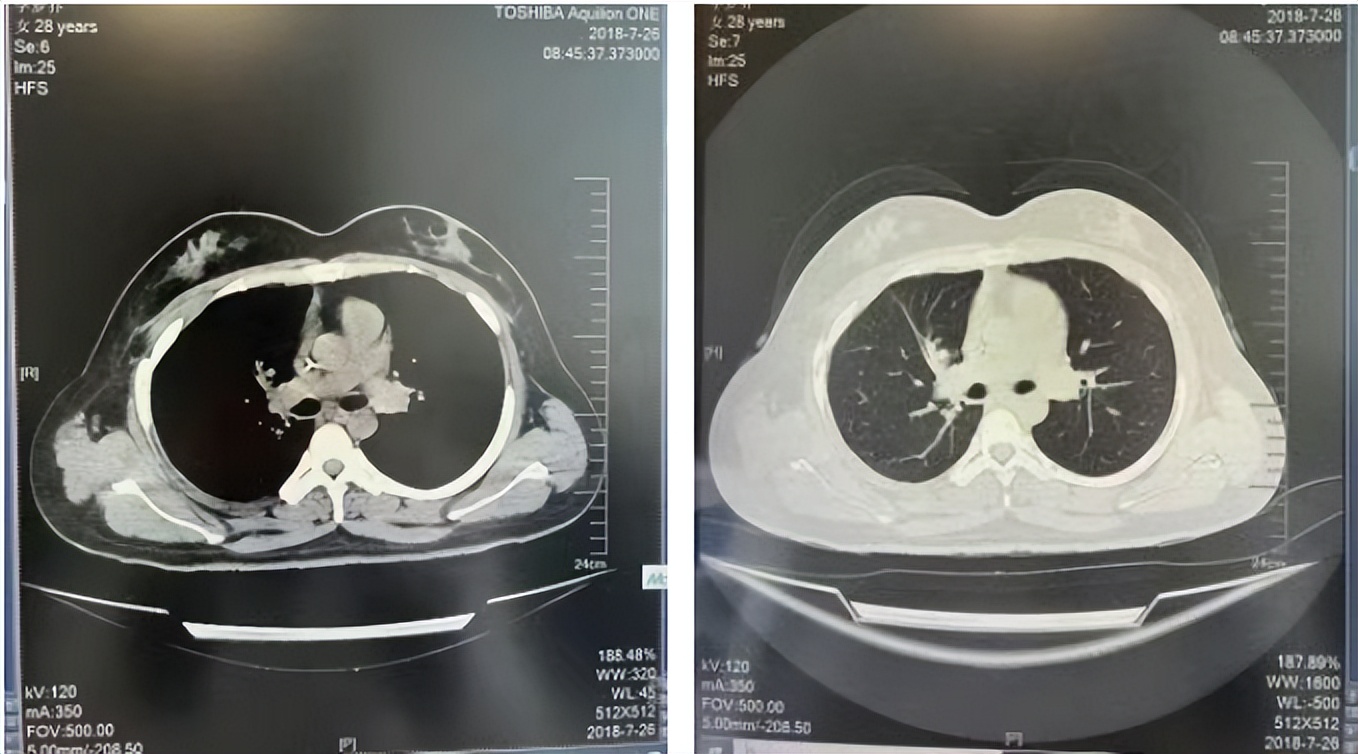

2016年1月复查CT提示支气管截断可见新发小结节,一线治疗采用培美曲塞+DDP方案化疗4周期(培美曲塞3.36,DDP 480mg)。化疗后复查胸部CT:右肺见不规则结节样影,最大层面大小约19mm*8mm,较前比较明显增大,疗效评估PD。2017.3-2017.4予单药多西他赛化疗3周期,疗效评估SD。2018年5月末复查CT提示结节较前增大,评效为PD,2018年6-10月予多西他赛+CBP化疗4周期,疗效评估SD。2022年5月患者出现活动后气短,复查胸部CT示右肺膨胀不良;右侧胸腔积液增多。胸腔积液包埋病理示符合肺腺癌细胞。行NGS基因检测:EML4:exon13-ALK:exon20融合。PD-L1(克隆号22C3)TPS<1%。

临床诊断:右肺上叶恶性肿瘤rT0N0M1a IVA期(第9版分期);恶性胸腔积液。

诊疗经过:2022年5月始口服克唑替尼3个月,出现肝功能异常(DILI 2级伴临床症状),改用恩沙替尼靶向治疗至今,目前评效为维持PR。恩沙替尼应用期间出现轻度肝功能异常(DILI 1级),对症处理后好转。截止目前PFS 33个月。

2018.07

2022.05

2022.08

2023.05